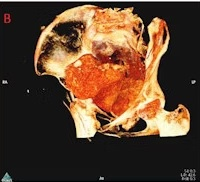

Radiologists help refute ‘pregnant mummy’ claim